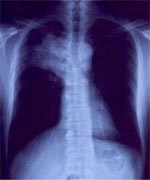

左写真:胸部エックス写真で、黒い部分が肺です。中央から向かって左に飛び出た部分が心臓です。

中央写真:向かって左側に白い部分があります。これは右肺がんです。

右写真:切除標本の切離面です。茶色か黒い部分が正常の肺で、乳白色の部分が肺がんです。気管支の中に入り込んでいるのが分かります。